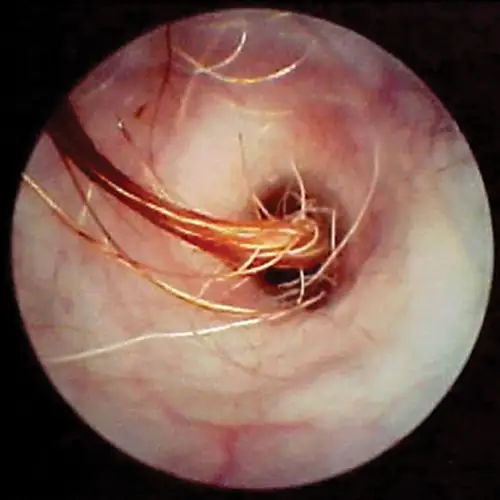

Ceruminoliths, concretions of dried medications, and foreign bodies are more often seen in the horizontal canal. Occasionally, epilated hairs will fall into the horizontal canal and become embedded in the thick wax accumulation along the floor of the horizontal canal. These hairs can be seen occluding the view of the eardrum (Figure 11).

selected slide image

FIGURE 11

1 / 2

Hairs in the horizontal ear canal obstructing the view of the eardrum